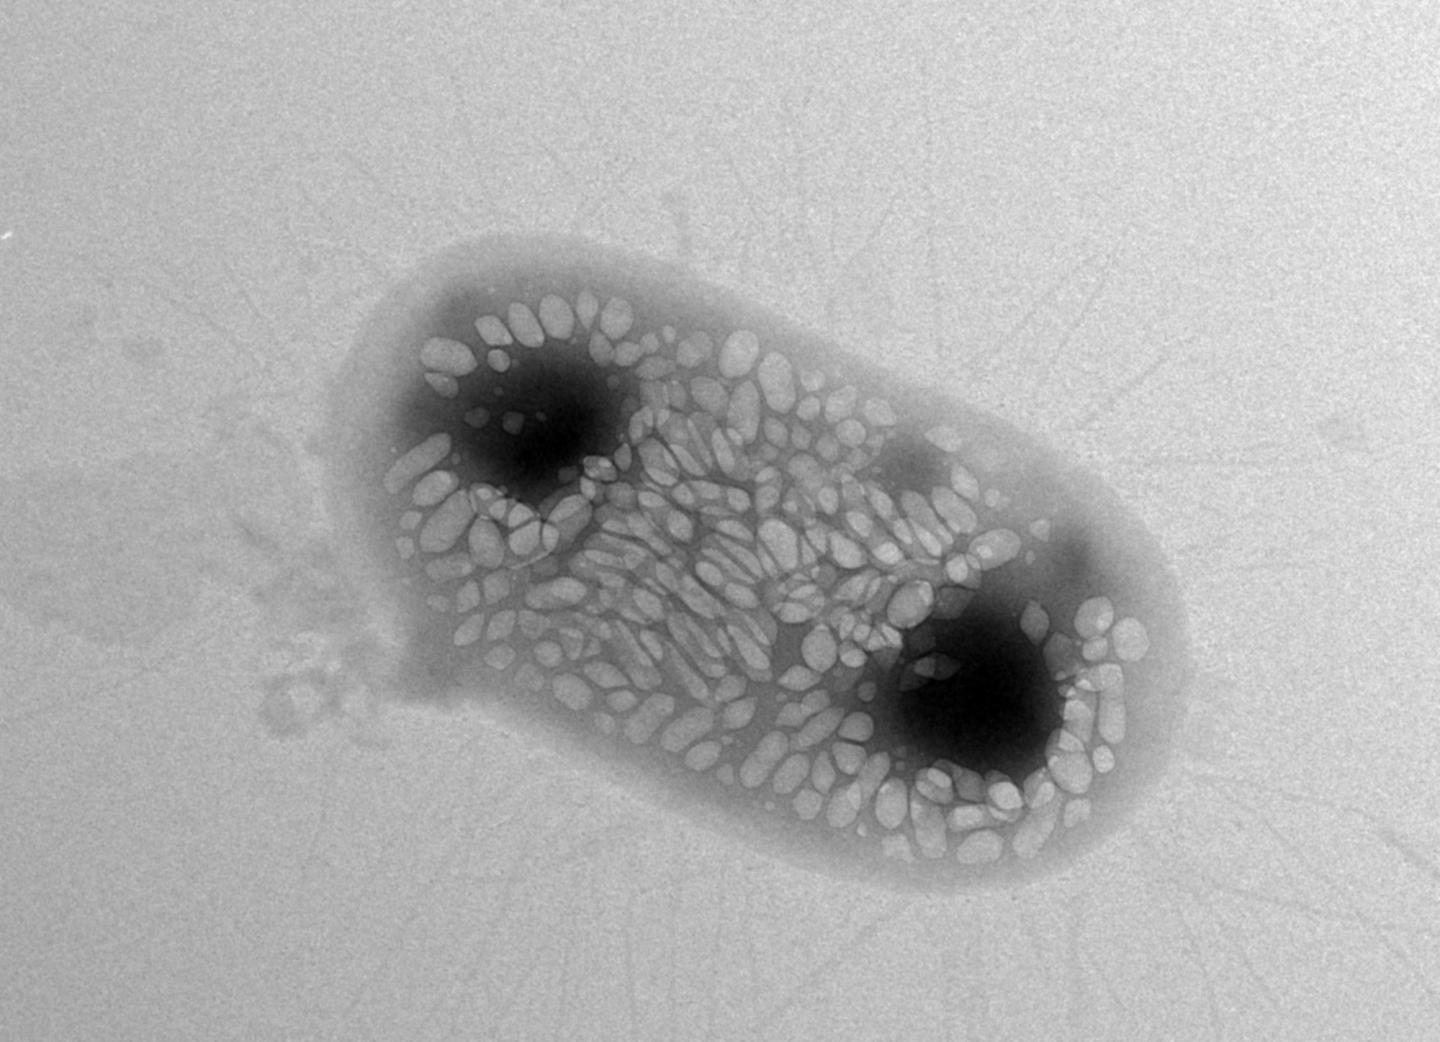

Shapiro wants to solve this problem with ultrasound techniques because sound waves can travel deeper into bodies. He says he had a eureka moment about six years ago when he learned about gas-filled protein structures in water-dwelling bacteria that help regulate the organisms' buoyancy. Shapiro hypothesized that these structures, called gas vesicles, could bounce back sound waves in ways that make them distinguishable from other types of cells. Indeed, Shapiro and his colleagues demonstrated that the gas vesicles can be imaged with ultrasound in the guts and other tissues of mice.

One of the challenges the team hit involved the transfer of the genetic machinery for gas vesicles into E. coli . They first tried to transfer gas-vesicle genes isolated from a water-dwelling bacterium called Anabaena flos-aquae, but this didn't work--the E. coli failed to make the vesicles. They tried again using gas-vesicle genes from a closer relative of E. coli , a bacterium called Bacillus megaterium. This didn't succeed either, because the resulting gas vesicles were too small to efficiently scatter sound waves. Finally, the team tried a mix of genes from both species--and it worked. The E. coli made gas vesicles on their own.

The gas vesicle genes code for proteins that act like either bricks or cranes in building the final vesicle structure--some of the proteins are the building blocks of the vesicles while some help in actually assembling the structures. "Essentially, we figured out that we need the bricks from Anabaena flos-aquae and the cranes from Bacillus megaterium in order for the E. coli to be able to make gas vesicles," says Bourdeau.